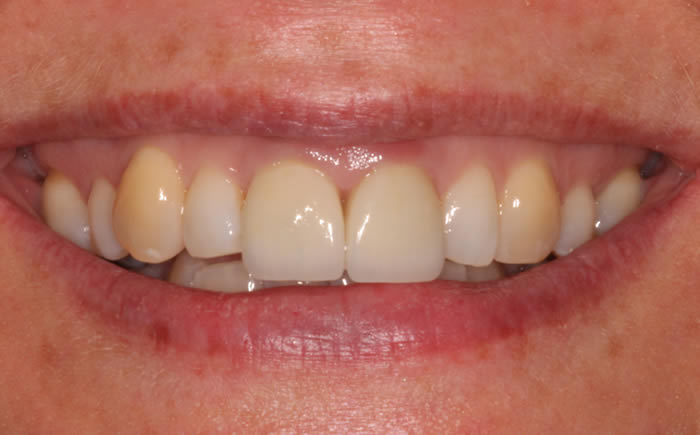

Before & After Gallery

More front teeth replaced by dental implants

Case Three (4 images)